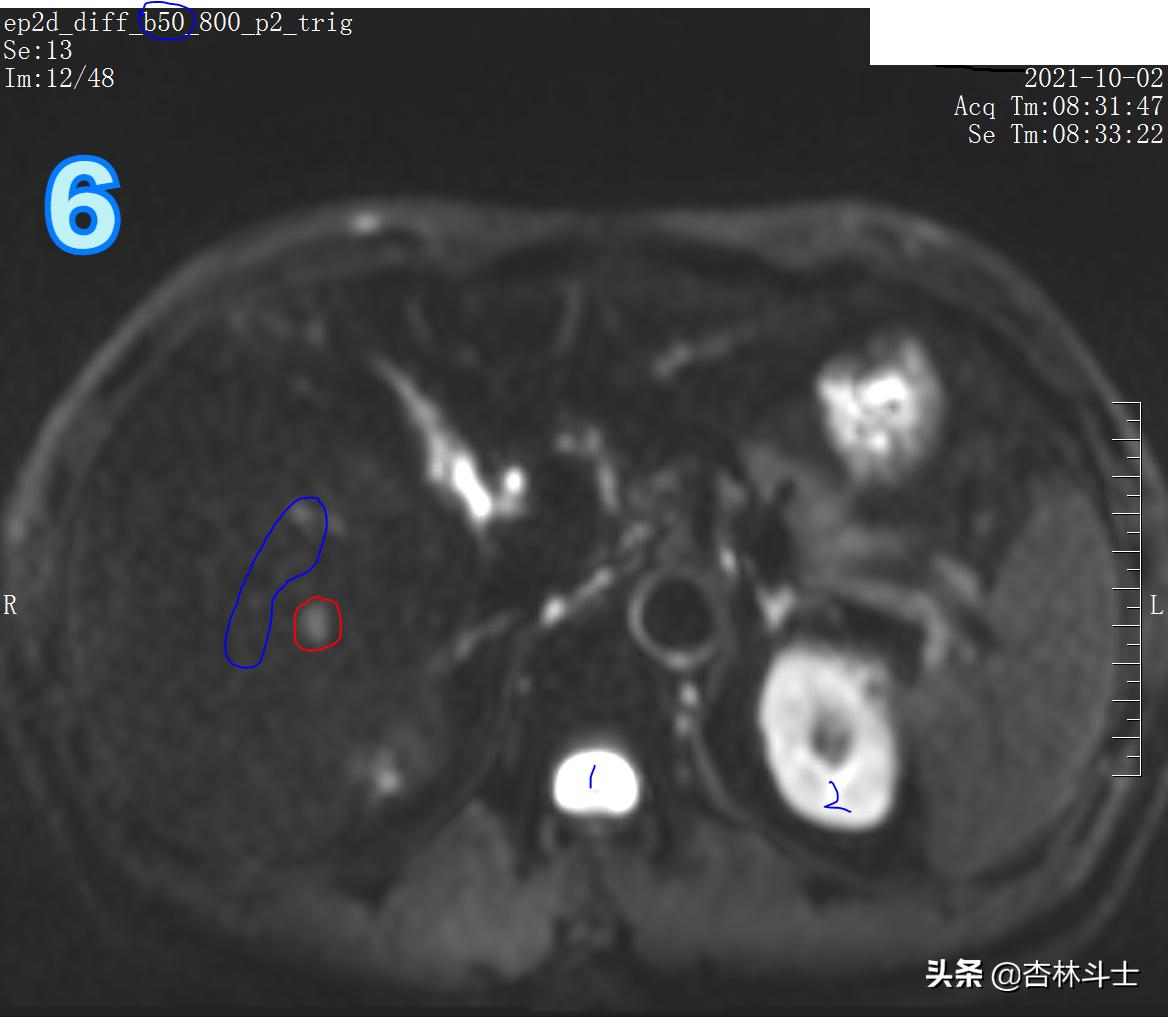

图6、7为弥散加权像,新发病灶在弥散加权上弥散受限,呈高信号。

总结:10月份复查,肝右后叶下段新发一个直径约1㎝的结节,T1呈等信号,T2呈稍高信号,弥散加权序列可见弥散明显受限,增强动脉期明显均匀强化,门静脉期出现对比剂廓清,呈略低信号,平衡期信号进一步减低,肝胆特异期未见特异性对比剂摄取呈低信号。增强特征为典型的“快进快出”,影像学上典型的肝细胞癌表现。